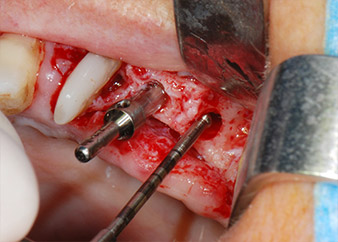

However, we maintained our initial plan to retain both teeth as temporary bridge abutments during the six-months osseointegration period of the implants. At reentry, the situation would have to be reassessed. First, in an attempt to manage the endo-perio problem, the remaining root surface was carefully debrided with piezoelectric equipment (Piezomed, W&H, used with the spatula-shaped insert S1, originally designed for erosion of the lateral sinus wall) (Fig. 4).

Then the apex was abraded with the same instrument to remove residual infected apical tissue and to reduce possible accessory root-canal ramifications (apicoectomy) (Fig. 5). A retrograde filling was not necessary because the orthograde filling had just been revised.